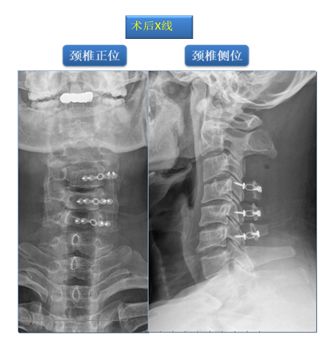

其后按计划实施我院特色术式:改良精准微创式颈椎椎板成形术(该技术是在梁徳主任指导下由江晓兵副教授改良),手术按照标准化流程下进行,术中耗时60分钟,出血量约50 ml。术后复查如下:

术后MRI可见椎管内空间增大,脊髓后移退让,脊髓周围受压完全解除,术后患者双下肢乏力症状彻底消失。

术后随访3月,患者为自己良好的康复而点赞

回顾案例治疗经过,患者术前经过2-3次治疗后,筋骨失衡相应症状已消除,之后再行手术治疗解除脊髓压迫,患者术后脊髓受压症状亦彻底消除。患者不禁感叹“这家医院就是牛,不仅帮我把神经压迫解除了,还把我的全部症状都解决了”。这就是我院脊柱骨科的特色,理筋正骨手法与外科手术产生了奇妙的融合,为患者提供了一套可以兼顾标本、筋骨并重的治疗体系。